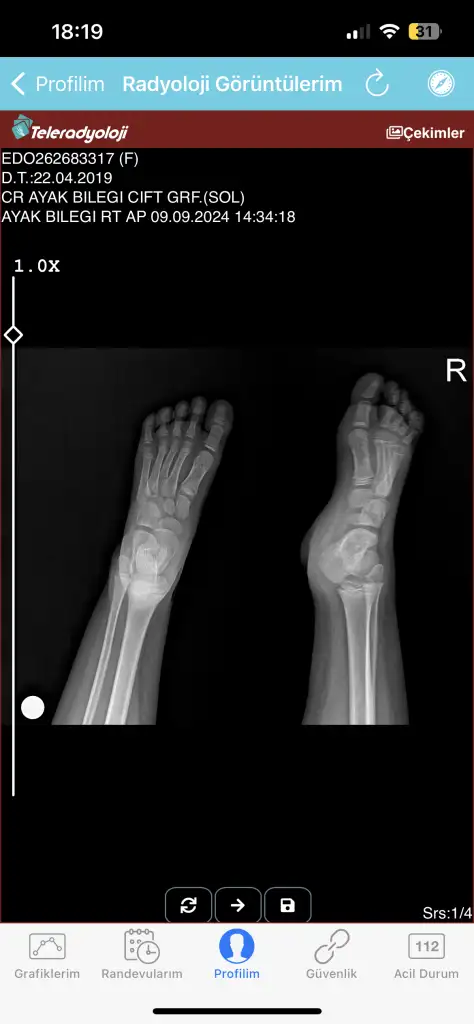

Merhaba benim kızım 4 gün önce bisikletten düştü ve ayağı yaralandı şişti doktora götürdüm doktor röntgen çekti röntgende pek bir şey görünmedi pansuman yapıp yolladılar iki gün sonra yani bugün pansumanını açtım ayağı daha kötü olmuş ve şişmişti kesinlikle üstüne basamıyor ve dokun durmuyor bugün yine gittim röntgen ve tomografi çekti tomografi raporunu ve röntgeni ekliyorum acaba anlayan bilen var mı bilen varsa yazabilir mi rica etsem ayağı çok kötü durumda çünkü korkuyorum bir şey olur diye

Kirik yok, catlak da yok, yumuşak doku zedelenmesi var. O da oldukca agri yapar cok yasamisligim var.

Agri kesici kullanmasi gerekebilir.